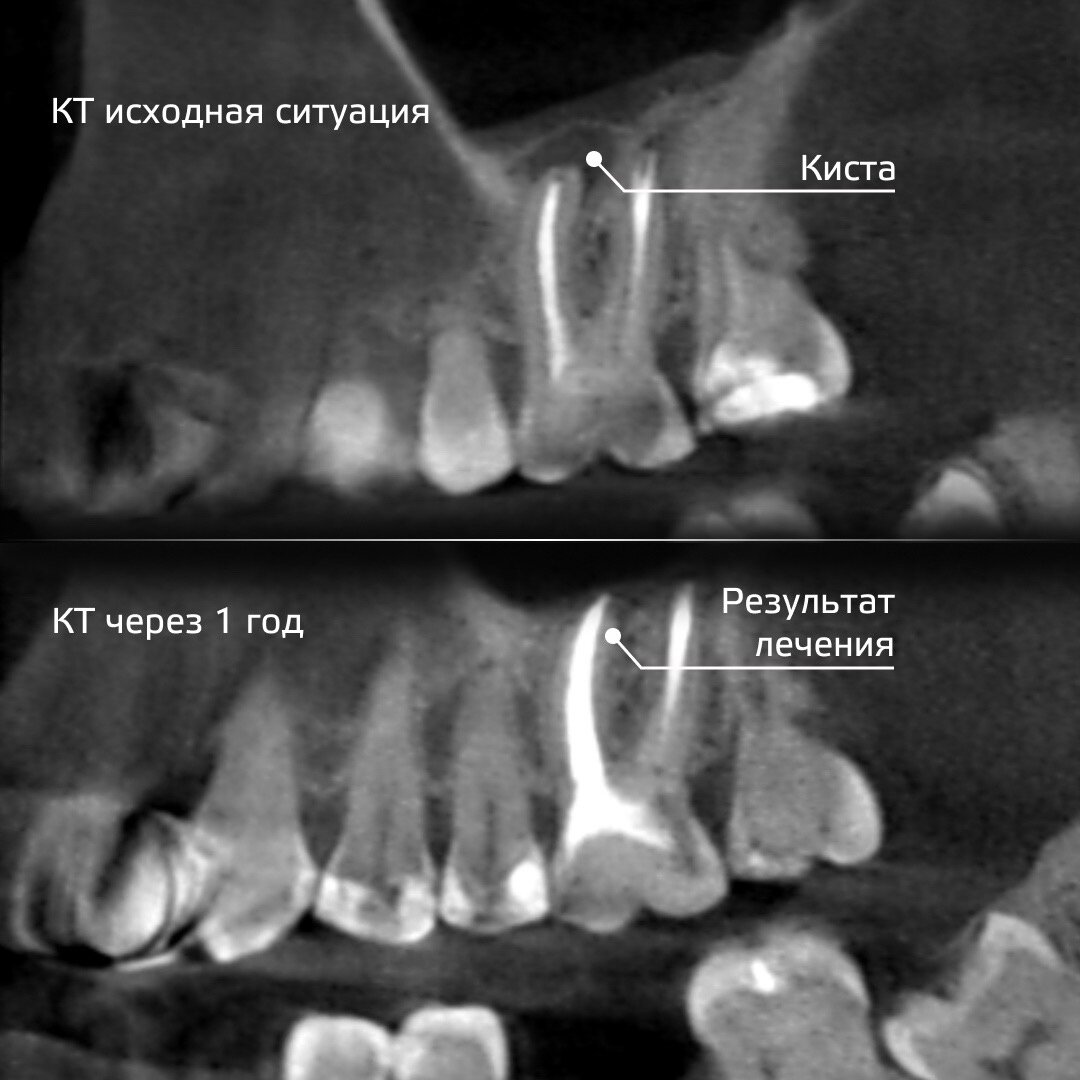

В Киостом обратился пациент по рекомендации врача-стоматолога из другой клиники. Случай был сложным, и действующий лечащий врач принял решение не рисковать, а направить пациента к нам, чтобы провести качественное лечение и сохранить зуб. При детальном обследовании выяснилось, что на корне 16-го зуба образовалась киста. При этом болевых ощущений человек не фиксировал.

После успешного лечения пациент вернулся к своему действующему врачу, но не терял контакт со специалистами нашей клиники для отслеживания ситуации. Через год сделали контрольный рентгеновский снимок, который показал полное заживление и восстановление костной ткани.